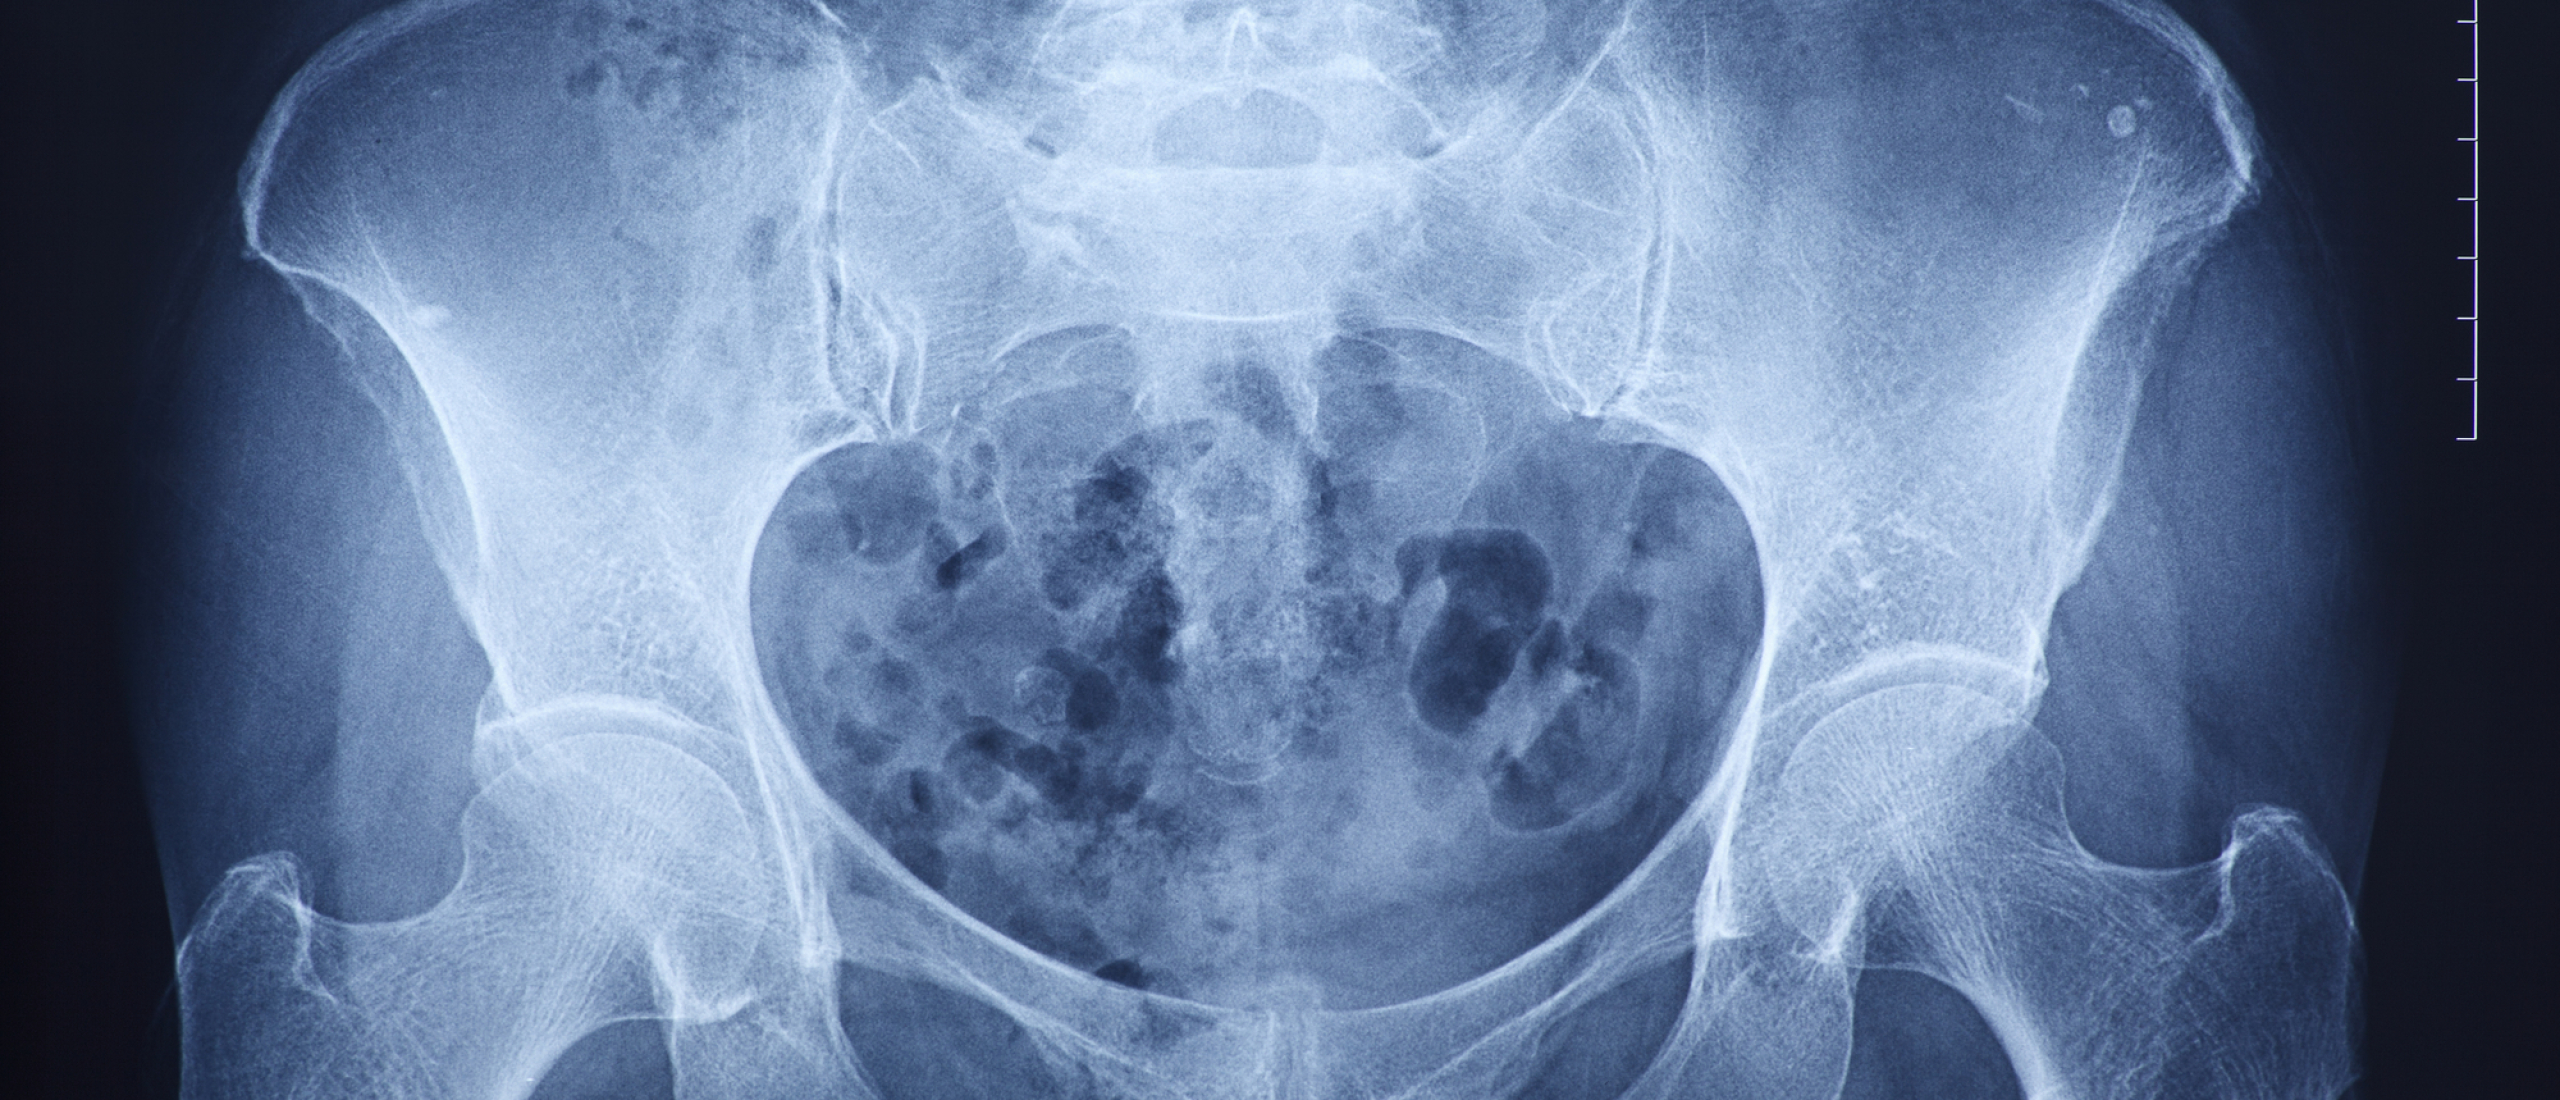

Rugklachten kunnen op verschillende manieren ontstaan na een ongeval. Denk aan een aanrijding, een val van hoogte of een bedrijfsongeval. Door de plotselinge kracht op het lichaam kunnen spieren, banden, tussenwervelschijven of zenuwen beschadigd raken. Soms zijn de klachten direct merkbaar, maar het komt ook regelmatig voor dat rugpijn pas dagen of weken later ontstaat.

Bij rugklachten door ongeval gaat het niet alleen om ernstige letsels zoals hernia’s of wervelfracturen. Ook langdurige spierklachten of instabiliteit van de rug kunnen grote impact hebben op je leven en werkvermogen.

Bij rugklachten speelt medische documentatie een grote rol. Huisartsverslagen, rapportages van specialisten en fysiotherapeuten helpen om inzichtelijk te maken hoe jouw klachten zich hebben ontwikkeld. Consistente medische vastlegging vergroot de kans dat rugklachten door het ongeval worden erkend.